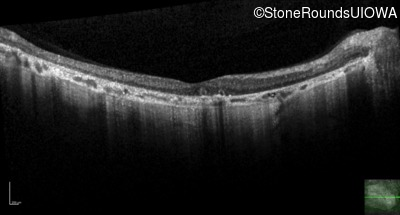

Optical Coherence Tomography - Right - 10/200

Exemplar / OCT Stack